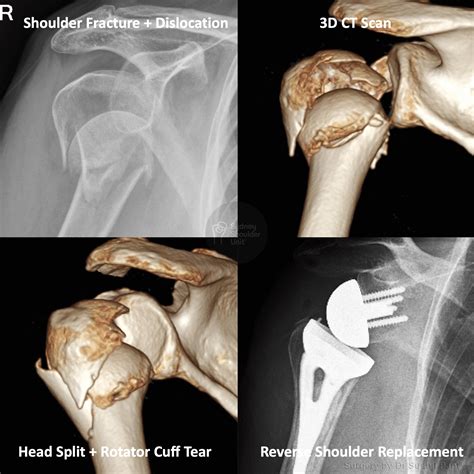

Diagnosing a displacement bone fracture typically involves a combination of physical examination and imaging tests. The diagnostic process usually includes:

• X-rays: These are the primary imaging tool used to visualize the bone and determine the extent of the fracture and displacement.

• CT scans: For more detailed images, especially in complex fractures, a CT scan may be ordered.

• MRI scans: These can provide information about soft tissue damage and are sometimes used in conjunction with X-rays and CT scans.

• Reduction: This involves realigning the bone fragments, which can be done manually (closed reduction) or surgically (open reduction).

• Surgery: In severe cases, surgery may be required to realign the bone fragments and stabilize them with plates, screws, or rods.